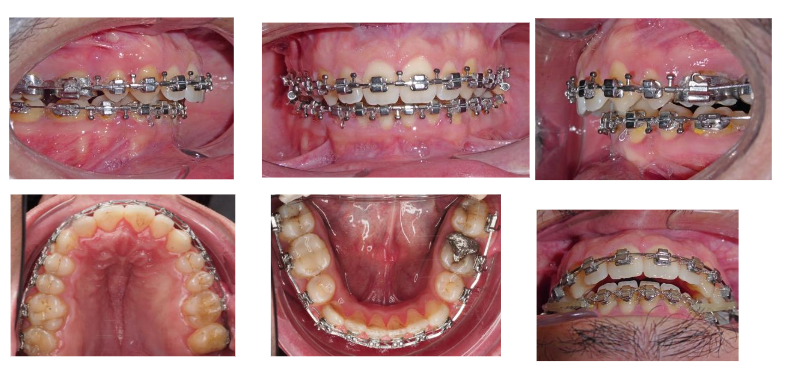

The treatment plan began with the extraction of teeth 34 and 44, as well as all four third molars, as part of the orthodontic preparation phase.

A multidisciplinary consultation was conducted, involving both the orthodontics and maxillofacial surgery teams, to establish a comprehensive treatment approach for the patient’s severe mandibular retrognathism and obstructive sleep apnea (OSA).

A surgical treatment plan was established and accepted by the patient. The primary objective was to perform a maxillomandibular advancement (MMA) to correct the pronounced mandibular retrognathism, increase the upper airway volume, and thereby treat the OSA. The surgical procedure consisted of a bimaxillary osteotomy, including a Le Fort I impaction, maxillomandibular advancement, and a complementary genioplasty.

The orthodontic phase of the treatment included dental alignment and leveling, correction of dental rotations, retraction of the lower incisors, and final coordination of both arches. Simulation models were used to optimize the relationship between the upper and lower dental arches. After the orthodontic preparation, a significant improvement in anteroposterior projection was observed.